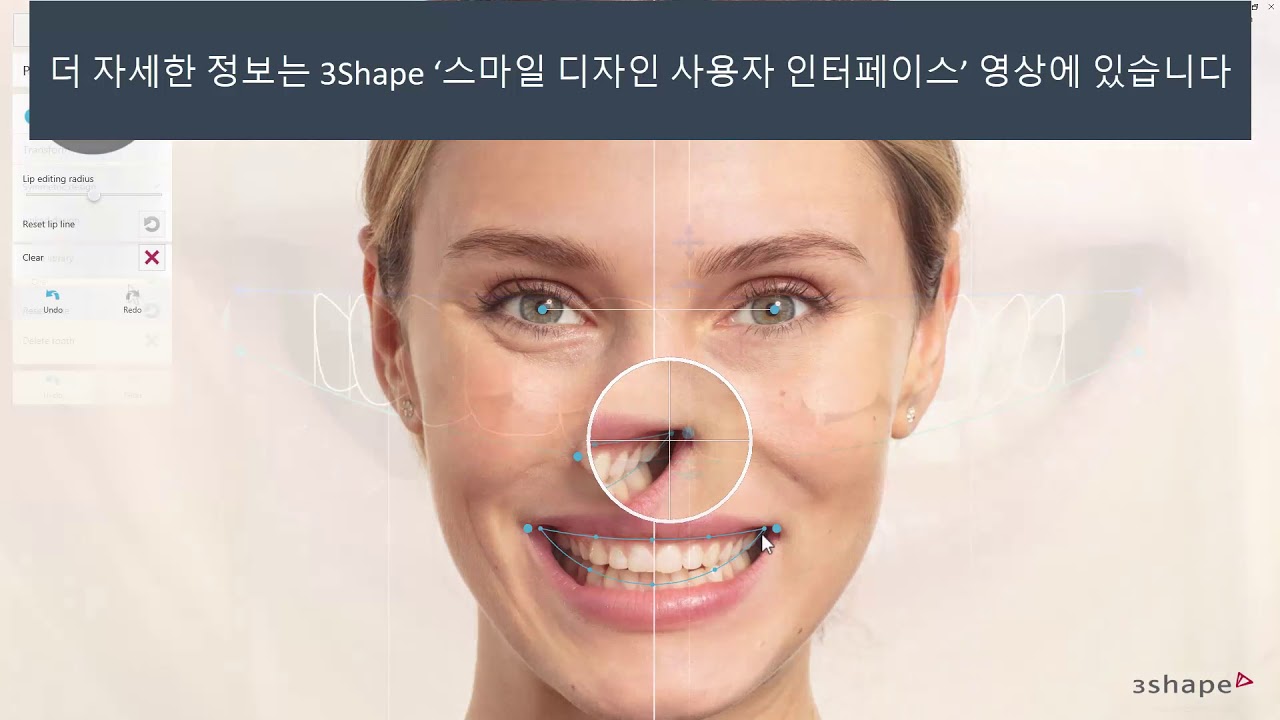

3shape Smile Design

Immerse yourself in the artistic beauty of 3shape Smile Design through substantial collections of inspiring images. blending traditional techniques with contemporary artistic interpretation. transforming ordinary subjects into extraordinary visual experiences. The 3shape Smile Design collection maintains consistent quality standards across all images. Ideal for artistic projects, creative designs, digital art, and innovative visual expressions All 3shape Smile Design images are available in high resolution with professional-grade quality, optimized for both digital and print applications, and include comprehensive metadata for easy organization and usage. Our 3shape Smile Design collection inspires creativity through unique compositions and artistic perspectives. Instant download capabilities enable immediate access to chosen 3shape Smile Design images. Our 3shape Smile Design database continuously expands with fresh, relevant content from skilled photographers. The 3shape Smile Design collection represents years of careful curation and professional standards. Diverse style options within the 3shape Smile Design collection suit various aesthetic preferences. Multiple resolution options ensure optimal performance across different platforms and applications. Professional licensing options accommodate both commercial and educational usage requirements. Each image in our 3shape Smile Design gallery undergoes rigorous quality assessment before inclusion. Time-saving browsing features help users locate ideal 3shape Smile Design images quickly. Advanced search capabilities make finding the perfect 3shape Smile Design image effortless and efficient.